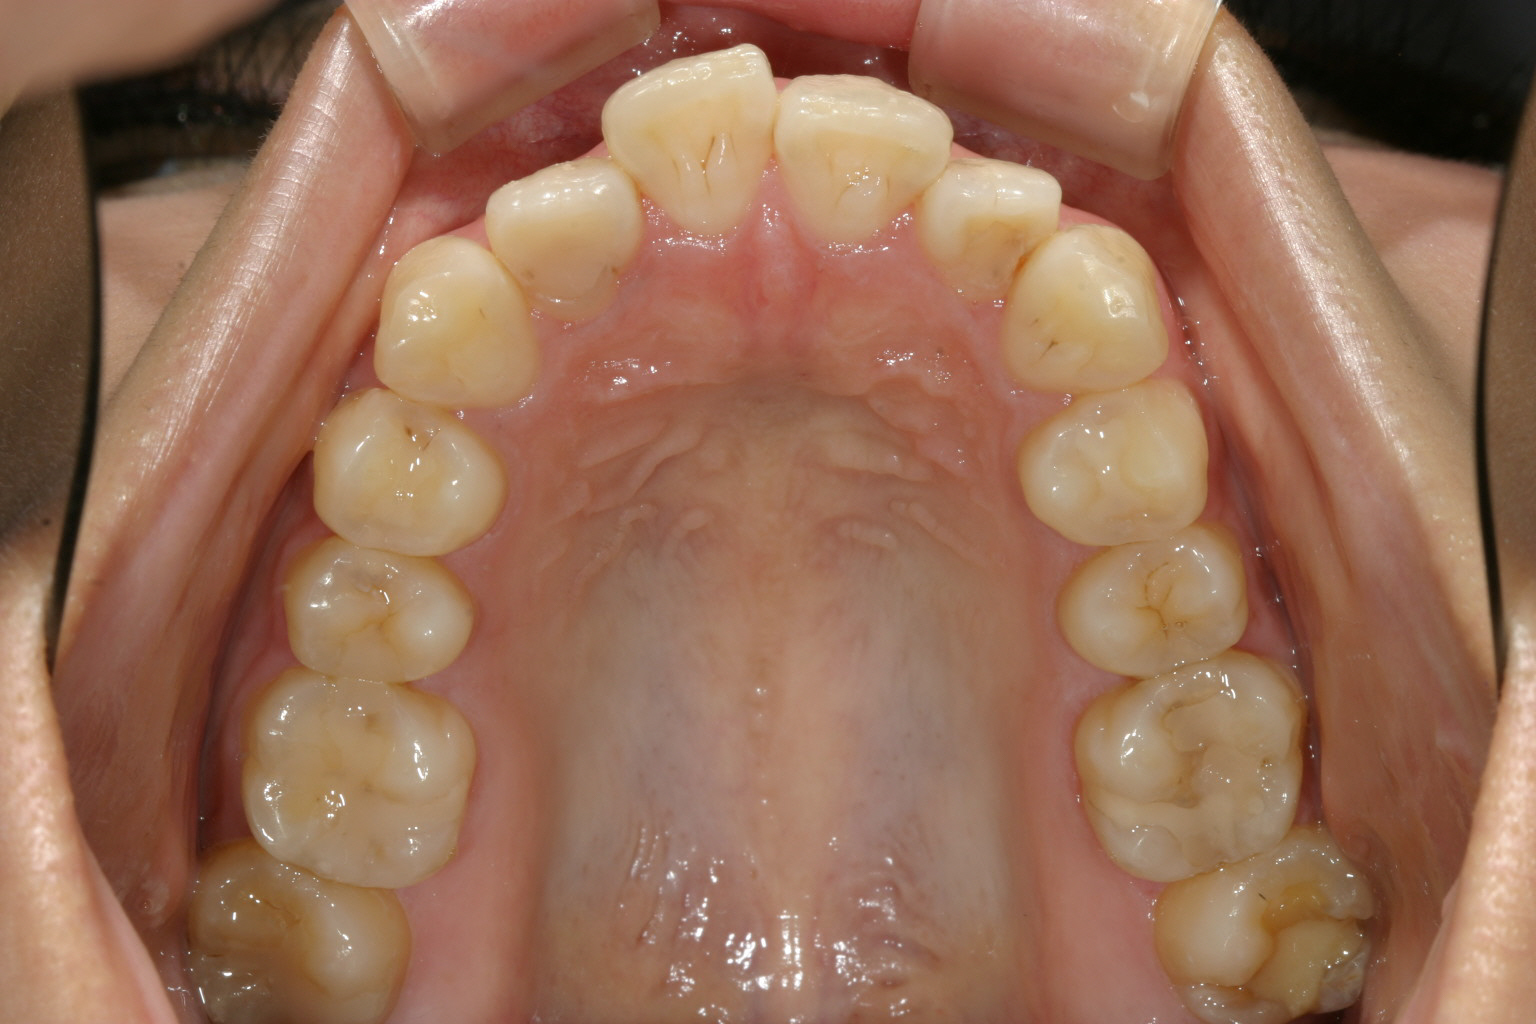

アーチか狭く前歯部が飛び出しています。

アーチを広げ、IPR(歯と歯の隙間を削る)を加え 出っ歯を改善しました。